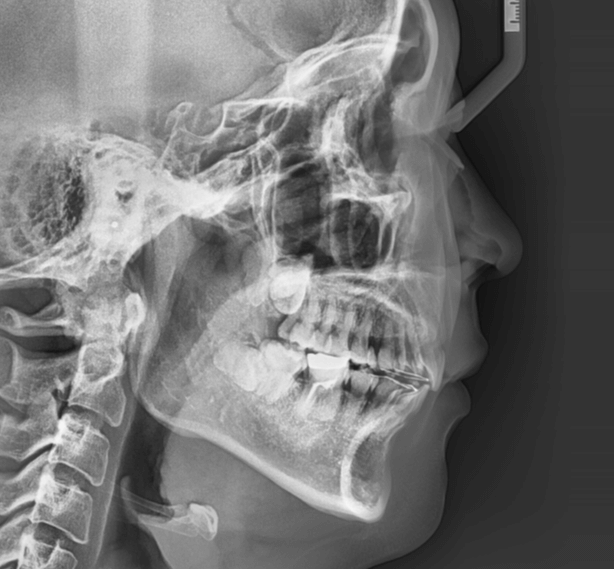

| 年齢・性別 | 25歳女性 |

|---|---|

| 主訴 | 前歯の歯並びの乱れ(叢生)を気にされて来院された25歳女性。咬み合わせや審美的な改善を希望されていました。 |

| 治療期間・回数 | 4年5ヶ月・30回 |

| 費用 | 1100,000円(税別) |